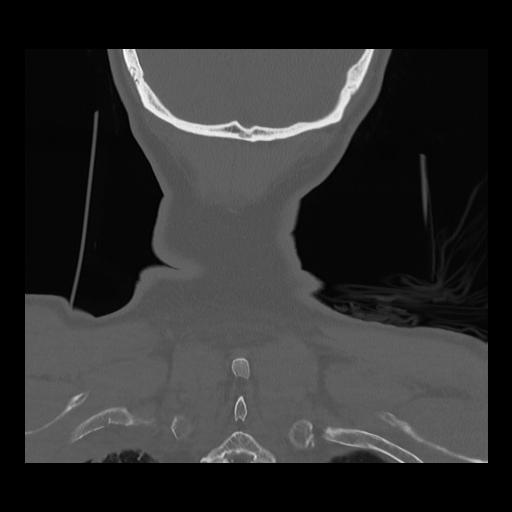

16 HUESO,,Coronal,2.000,HUESO,Coronal,